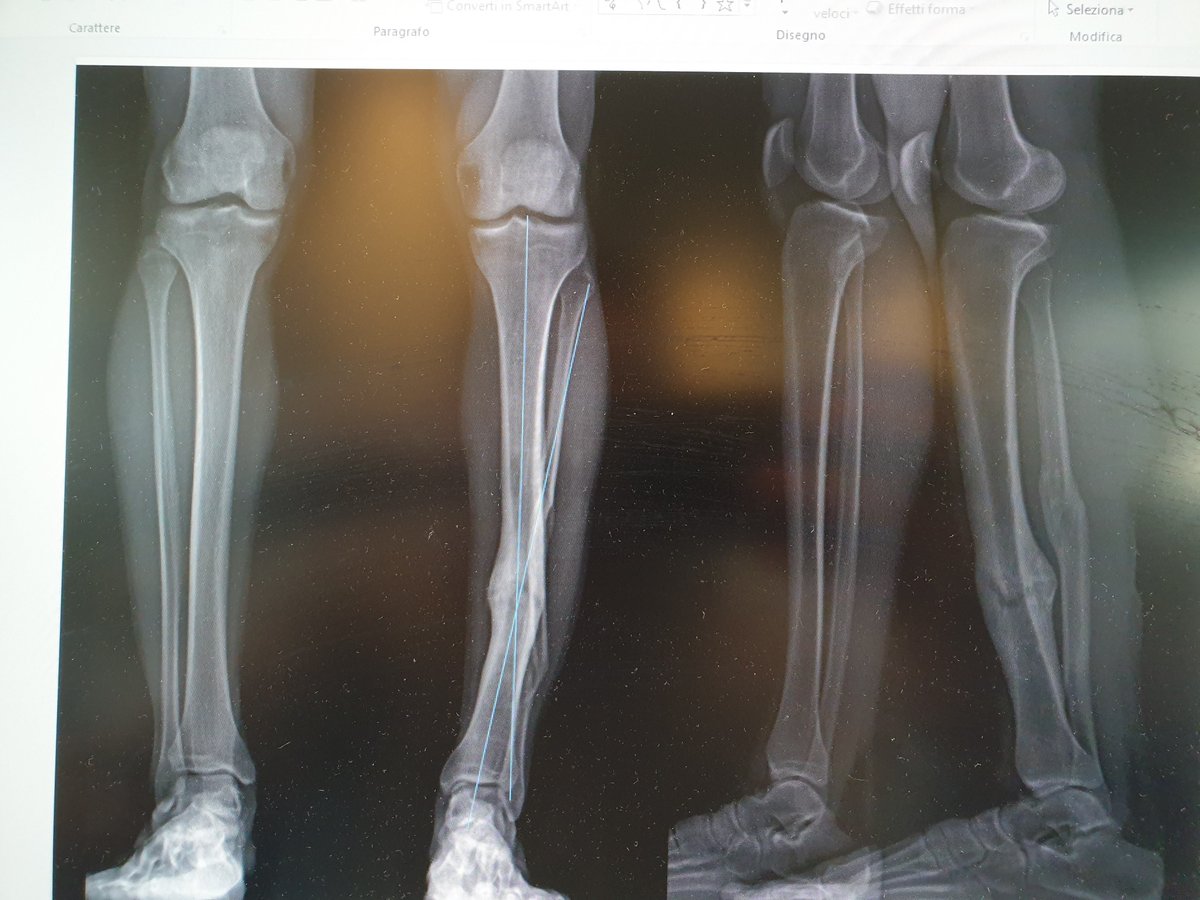

عمليات #تطويل #العظام من العمليات الأمنة والناجحة بنسبة كبيرة في حال التزم المريض بتعليمات الجراح والعلاج الطبيعي.. الصورة لعملية تطويل عظمة الساق 5 سم بجهاز smart #TSF